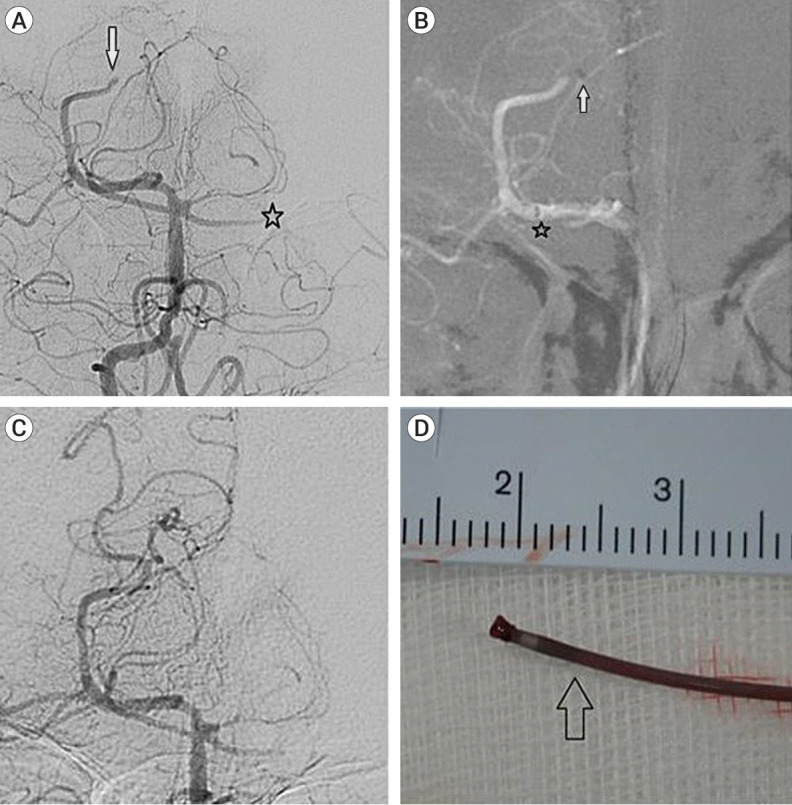

众所周知,机械血栓切除术对远端中血管闭塞(DMVO)和大血管闭塞都很有效,但迂曲的DMVO容易在支架回流血栓切除术中造成血管损伤。此外,在使用专用抽吸导管进行抽吸血栓切除术时,可能很难接触到血栓。大多数研究都描述了使用支架取栓器和专用抽吸导管治疗 DMVO 的情况,但使用微导管抽吸血栓切除术治疗 DMVO 的研究报告还很有限。在此,我们描述了三例使用微导管进行抽吸血栓切除术治疗 DMVO 的病例,随后显示出良好的效果。因此,使用微导管抽吸血栓切除术是治疗迂曲DMVO的另一种可行方法。

While mechanical thrombectomy is known to be effective for distal medium vessel occlusion (DMVO) as well as large vessel occlusion, tortuous DMVO are predisposed to vessel injury during stent retriever thrombectomy. Furthermore, getting access to the thrombus may be difficult during suction thrombectomy using a dedicated suction catheter. Most studies describe DMVO treatment using stent retrievers and dedicated suction catheters, but there are limited studies reporting DMVO treated with suction thrombectomy using a microcatheter. Herein, we describe three cases of DMVO treated with suction thrombectomy that was performed using a microcatheter and subsequently showed good results. Therefore, suction thrombectomy using a microcatheter is a viable alternative treatment for tortuous DMVO.